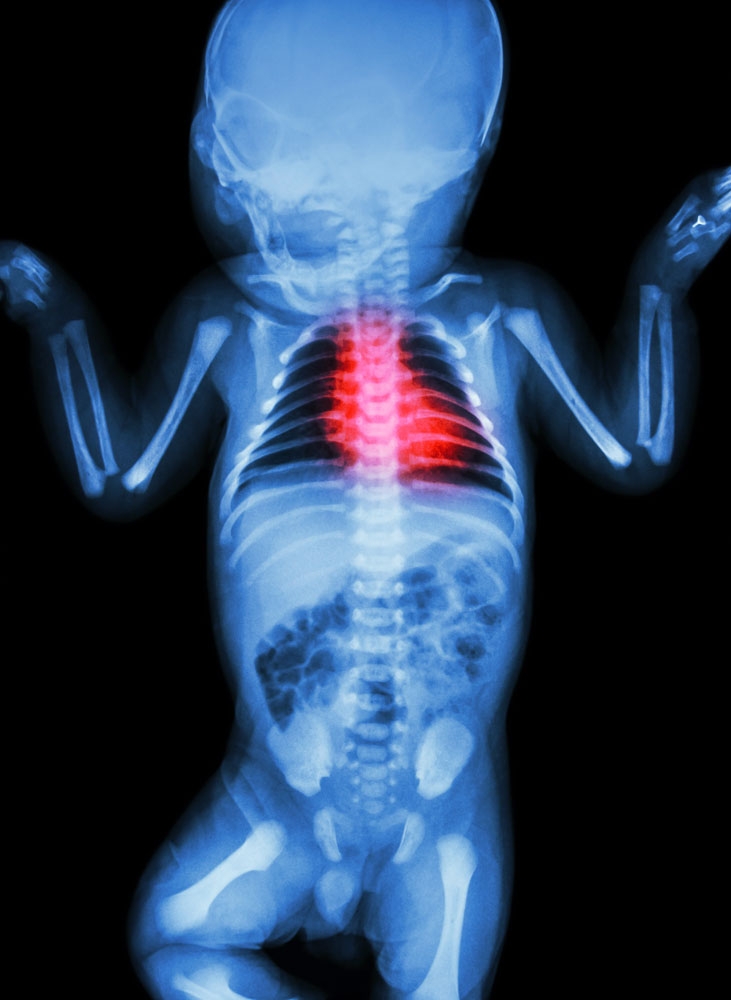

兒童那些疾病需要做X線檢查

在醫(yī)院,我們經(jīng)常會遇到患兒家長唯恐X線傷及小兒身體而放棄檢查,導(dǎo)致延誤疾病的診斷與治療。眾所周知,X線對人體是有害的,大劑量的X線的確能損害人體部分白細(xì)胞,但目前國內(nèi)外X線都是經(jīng)過嚴(yán)格驗(yàn)收,所有設(shè)備的使用都在安全范圍之內(nèi),而且檢查時,醫(yī)生會盡量減少照射劑量,以保護(hù)患兒身體健康。  那些兒科疾病需要做X線檢查呢?

新生兒疾病

由于新生兒的生理特點(diǎn),一般臨床檢查往往不能準(zhǔn)確地判斷其所患疾病,這樣就會延誤治療,因此,若新生兒為早產(chǎn)、難產(chǎn)兒、或有生后窒息,患兒出現(xiàn)呼吸困難、面色青紫、口吐白沫、精神不好,應(yīng)速到??漆t(yī)院拍胸片檢查。如發(fā)生新生兒出生后不能吃奶,并有持續(xù)性嘔吐,吐粘痰,腹部紅腫膨隆等情況,一定要去醫(yī)院X線攝片幫助診斷與治療。

骨骼系統(tǒng)疾病

絕大多數(shù)骨骼系統(tǒng)的疾病都需要拍攝X線片來進(jìn)行診斷。這類疾病有些是骨骼本身的病變,另一類是遺傳性疾病、代謝性疾病以及血液疾病等均能在骨骼系統(tǒng)中表現(xiàn)異常X線征象,所以拍攝骨骼系統(tǒng)X線片是十分重要的,拍片部位應(yīng)根據(jù)各種疾病表現(xiàn)不同部位而定,只有全面觀察病變情況,準(zhǔn)確判斷病變的種類,才有利于治療。